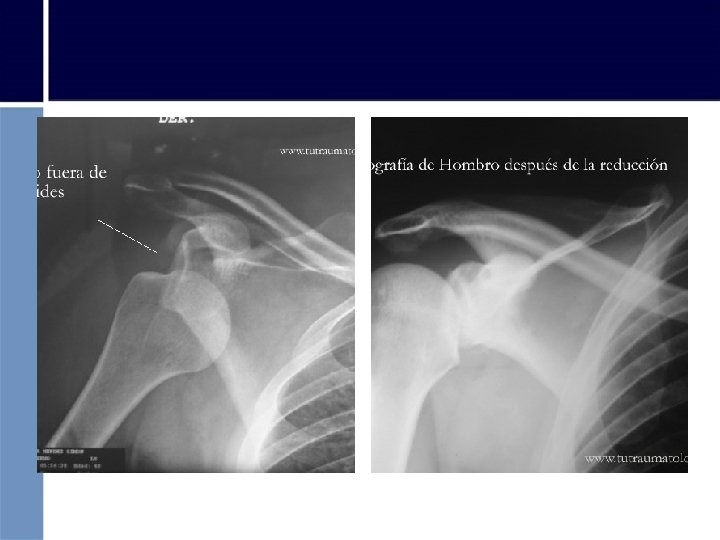

b) LUXACIÓN o DEFINICIÓN: Distensión de los ligamentos y cápsula articular con salida de un hueso o articulación de su lugar. Pérdida de contacto de las caras articulares de 2 o más huesos.

LUXACIÓN • Cualquier articulación es susceptible de luxarse. • Dedos, codos y hombros – Articulación menos estable > facilidad para luxar. • Cadera – Articulación muy estable superficies articulares se encuentran encajadas entre sí • Frecuencia de las lesiones se produce por: – Propia estructura – Condiciones de estabilidad – Fuerza de músculos y tendones que lo rodean.

¿Cómo reconocer una Luxación? • Inflamación y deformidad de la zona luxada • Dolor intenso que no cede • Incapacidad para movimiento de flexión y extensión • Equimosis

• Luxación hombro